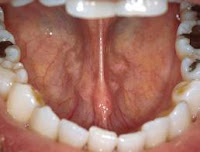

Inside of a tooth, under the white enamel and a layer called the dentin, is soft tissue called the pulp. The pulp contains blood vessels, nerves, and connective tissue.

Root canal therapy is necessary when the pulp becomes inflamed or infected. The inflammation or infection can have a variety of causes: deep decay due to bacteria, multiple dental procedures on the tooth, or a crack or chip in the tooth. In addition, trauma to a tooth may cause pulp damage even if the tooth has no visible chips or cracks. If pulp inflammation or infection is left untreated, it can cause pain, and/or lead to an abscess. Signs of pulp damage may include pain, prolonged sensitivity to heat or cold, discoloration of the tooth, and swelling and tenderness in the nearby gums. Sometimes there are no symptoms at all.